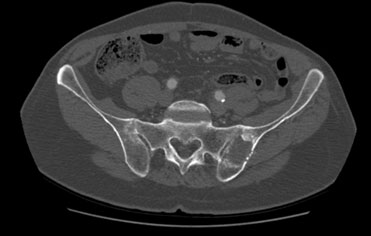

Kötü huylu kemik tümörlerinde ise sıklıkla kemik metastazı dediğimiz başka bir organdan kaynaklanan kanserin kemiğe sıçradığı durumlarda tercih etmekteyiz.

RF ablasyon işlemi bittikten sonra aynı giriş kanülünden kapalı çimento uygulaması özellikle omurga (vertebra) ve pelvis/asetabulum metastazlarında mekanik ve ağrı açısından ekstra avantaj sağlar. RF ablasyon çimentonun kemik içerisine daha homojen yayılmasına olanak sağlar. Bu yöntem kırık gelişmiş ya da kırık riski olan omurga kemiklerine (instabilite ve ciddi omurilik basısı durumunda önerilmez) uygulanabilir. Ablasyon işleminin tamamlanmasının ardından kemik çimento enjeksiyonu uygulanacak ise, doku ısısının düşmesi ve aşırı ısınmaya bağlı hasar gelişme ihtimalini önlemek amacıyla yaklaşık 15 dakika beklenmesi gerekir.